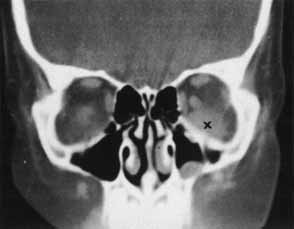

Of the adjunctive tests available, CT scan is the most useful in providing information about the presence and position of a foreign body relative to other structures in the orbit. Steel fragments 0.5 mm in diameter or larger74 and steel particles as small as 0.06 mm3 can be detected.75 Density measurements can be analyzed to distinguish metal, wood, glass, and air from surrounding tissue (Fig. 18). The appearance of wood may vary with the length of time in the orbit and the degree of hydration.76 In some cases, CT has not been able to detect wooden foreign bodies.77 Localization can best be achieved with the evaluation of axial and coronal views. Additional sagittal interpretations and three-dimensional reconstructions can be generated with available software.74 The diagnostic limitations of CT scans must be recognized; in some situations, accurate localization may be obscured by scatter artifact caused by metals or false-negative findings of radiolucent materials.

Fig. 18 A, Wood foreign body (arrow). B, Glass foreign body (arrow). C, Metal foreign body (arrow).